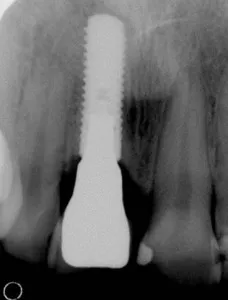

Antes del diente en deterioro con infección